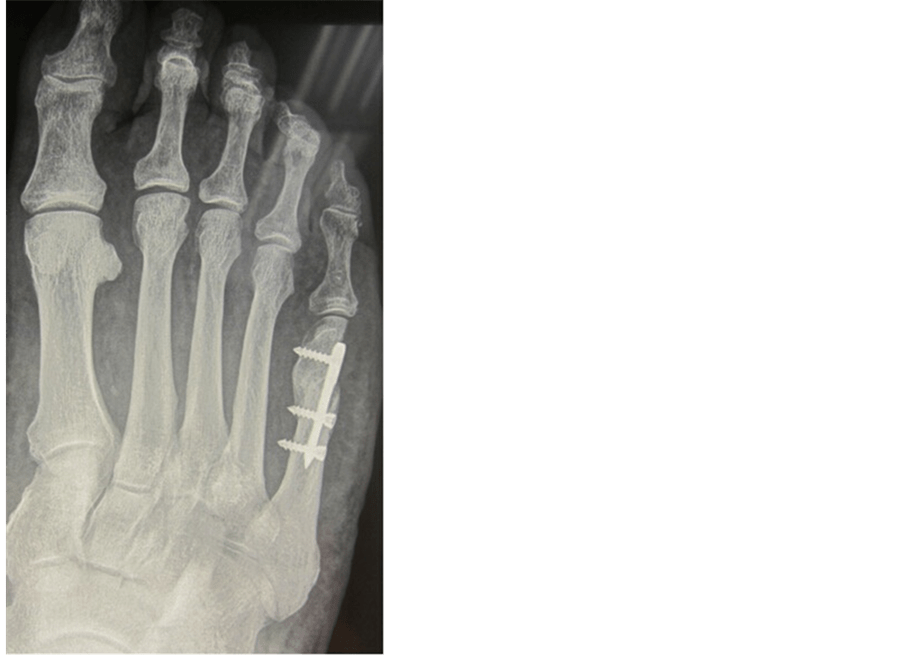

Osteotomy secured and covered. Download Scientific Diagram

Osteotomy secured and covered. Download Scientific Diagram Is Osteotomy Surgery Covered By Insurance There are lots of factors to consider when determining if your surgery qualifies for insurance coverage, such as the cost, the surgeon, the surgical office location, and. For some patients who have knee arthritis, this surgery can delay or prevent the need for a partial or total knee. Covers surgery (osteotomy) to remove a wedge of bone near a damaged. Is Osteotomy Surgery Covered By Insurance.